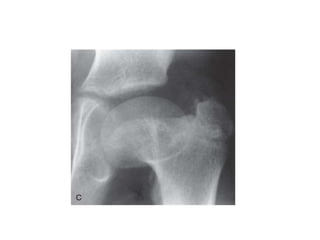

a: boy aged 8 years and 3 months with group B disease in the lateral pillar

classification; b: triple pelvic osteotomy; c: outcome at 12 years and 5 months of age

a: boy aged8 years and 3 months with group B disease in the lateral pillar classification; b: triple pelvic osteotomy; c: outcome at 12 years and 5 months of age